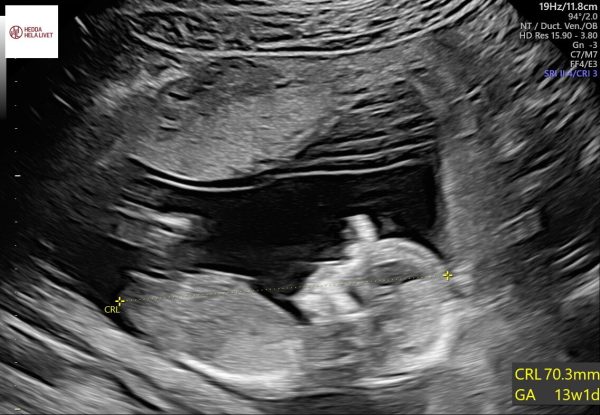

Idag hade Ida sitt första rutinultraljud där de kontrollerar olika organ, hjärtslag, kroppsdelar mm för att se att allt är som det ska. Allt såg bra ut ❤️ och barnmorskan gjorde en tidig bedömning av vilket kön barnet har…. med 70% sannolikhet är det en liten flicka 🩷 vi vet med säkerhet på ultraljudet i december.

Även denna gång följde Idas fina vän Diona med som stöd ❤️ beräknad förlossning kvarstår den 19 maj.